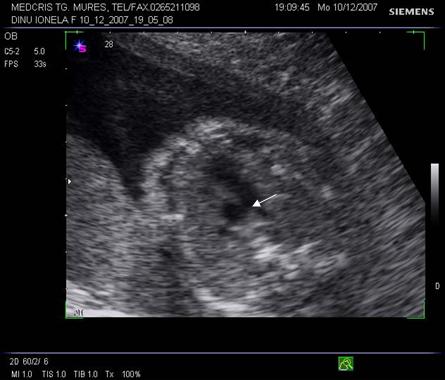

Fig. nr.176. Planul 0 de sectiune transversala ptr examinarea cordului, se incepe cu abdomenul , in care se remarca stomacul si aorta ( cu o sageata ) alaturi spre dreapta , vena cava inferioara ( cu doua sageti )